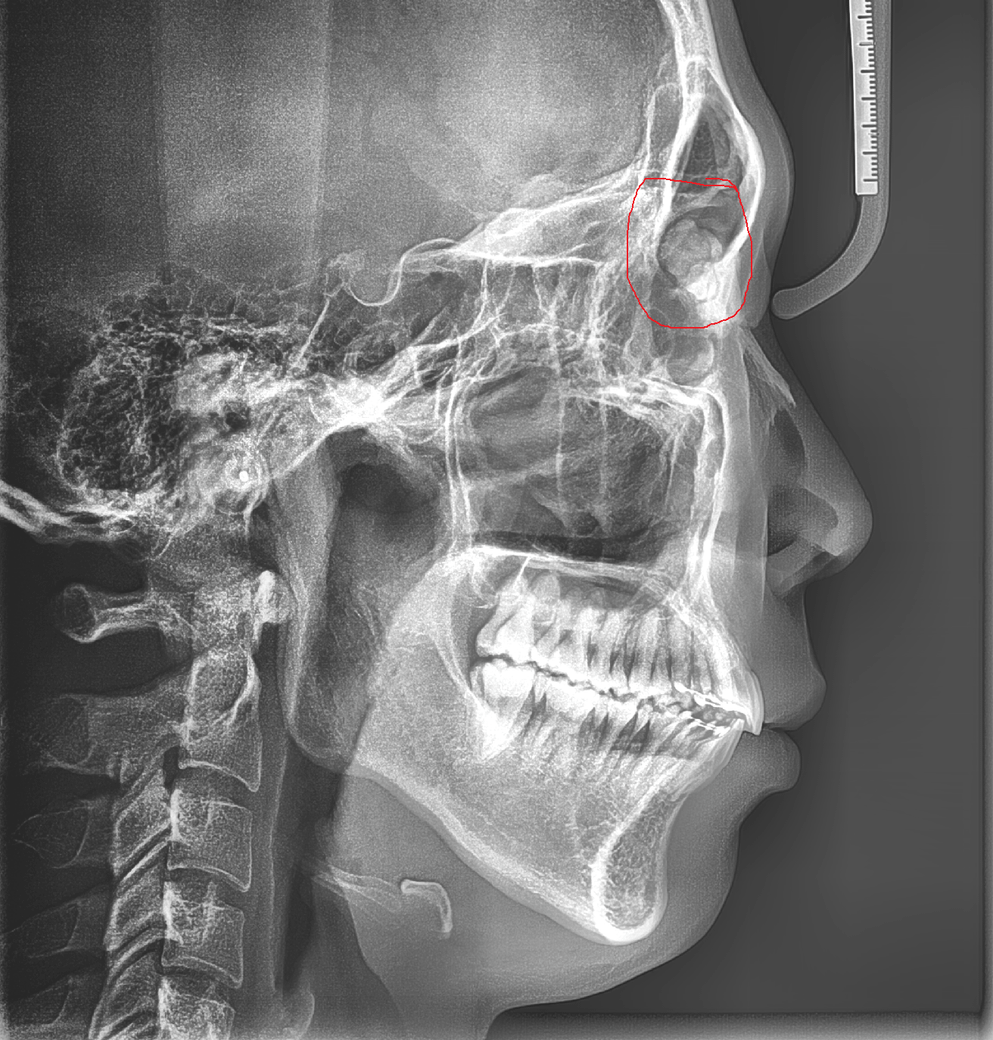

엑스레이 사진 결과 저 빨간색으로 표시한 부분이 다른 사람과 비교 했을때 없다고 하는데 무슨 물체가 보입니다

안와 공간에 X-ray 상으로 밝은 병변이 보입니다. 안과 혹은 이비인후과에서 진료를 보는것이 좋겠습니다.

현재 보이는 부분은 Frontal sinus 의 안쪽 공간으로 보이며 Sinus 아랫 부분에 종양처럼 보이는

병변이 관찰되나 부비동염 즉 충농증처럼 Sinus 에 차 있는 콧물 혹은 코가래의 가능성도 있습니다.

이비인후과 진료를 통해 Maxillary CT 를 찍어 확인하는 것이 필요한 것으로 보입니다. 감사합니다.

엑스레이를 보았을 때 두개골의 부비동 중 하나인 전두골동(frontal sinus)에 이물이 보입니다. 엑스레이 소견만으로는 무엇인지 명확하게 알 수 없어 CT 및 MRI 같은 정밀 검사가 필요해 보이십니다. 우선은 신경외과에서 정밀 검사 및 평가를 해보시는 것을 권고드립니다.

위치로는 전두부 부비동이라는 곳에 이상 음영이 관찰되는 것으로 보입니다. 정확한 확인을 위해서는 CT검사가 필요할 것으로 보이고 이비인후과에 가셔서 확인을 해 보시면 될 듯 합니다.